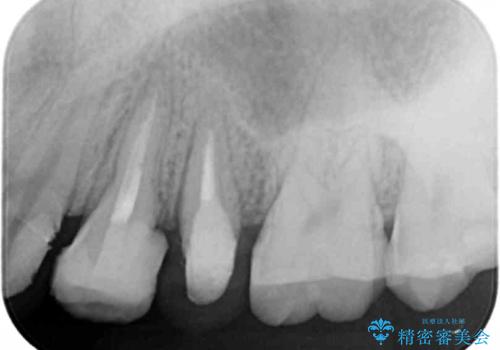

挺出小矯正を行った縁下カリエス治療

X線撮影を行い、隣接面に多発した虫歯と歯ぐきよりも深くなってしまった虫歯を小矯正をおこなったのちのセラミック治療で問題を解決します。